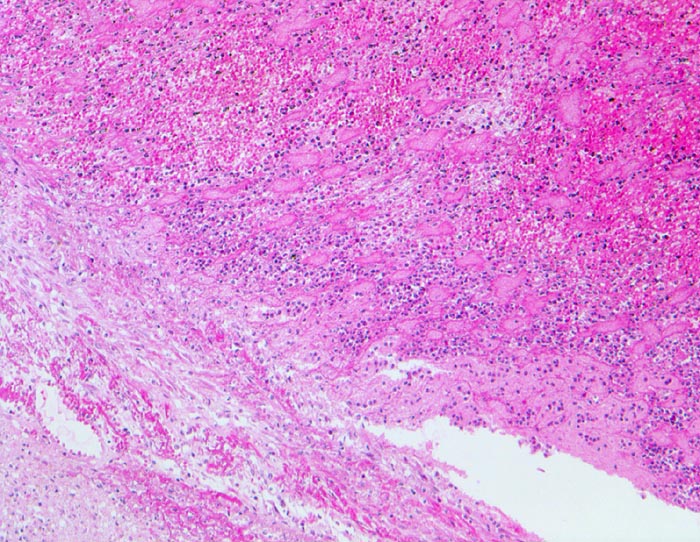

Parietalthrombose über Myokardinfarkt

Über dem Infarkt, dem Endokard aufgelagerter geschichteter Korallenstockthrombus bestehend aus Fibrin, Granulozyten und Erythrozyten.

Diagnose eines Myokardinfarktes vor 4 Tagen.

50